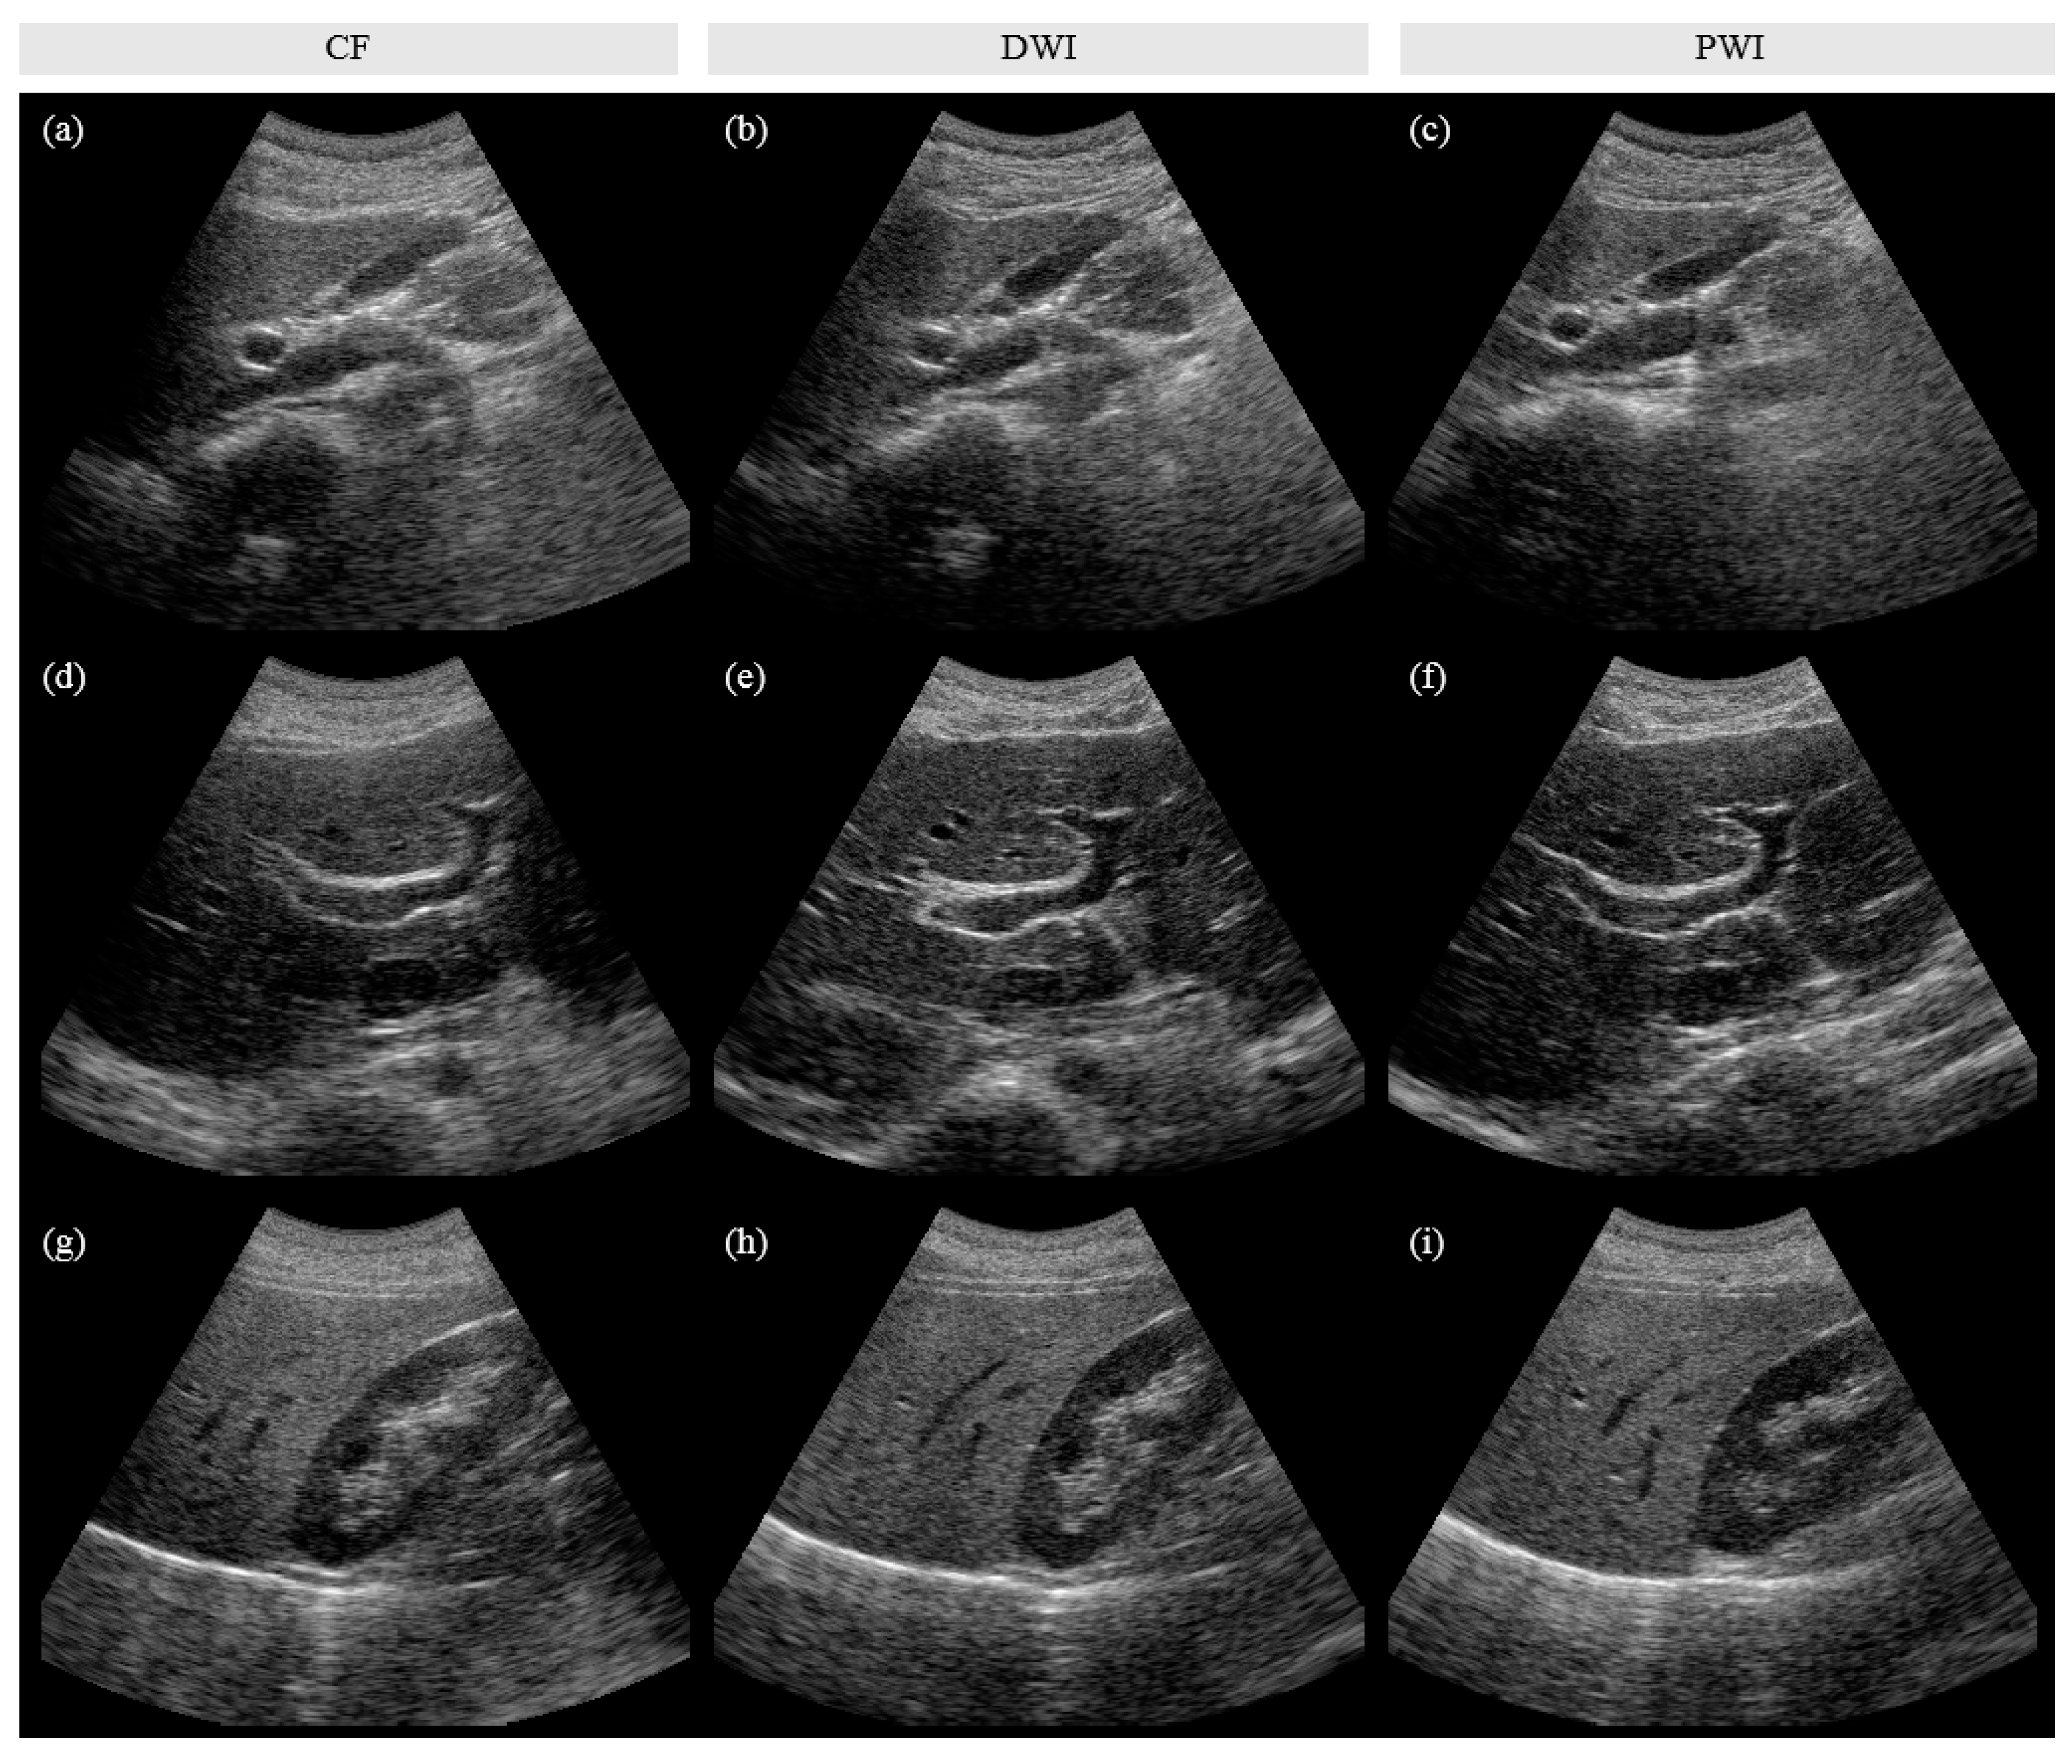

Figure 5.

Representative in vivo images of (a–c) gallbladder, (d–f) liver, and (g–i) kidney, which were reconstructed by using CF (for (a, d, g)), DWI (for (b, e, h)), and PWI (for (c, f, i)). PWI showed better image quality with a 4-fold higher acquisition frame rate than CF and provided a comparable performance with a 2.9 times lower number of computations compared to DWI.

Figure 5 shows representative gallbladder, liver, and kidney images obtained using CF, DWI, and PWI. Although slightly different cross-sections were captured across the imaging techniques, the overall image quality, including the spatial resolution and image contrast, is better in DWI and PWI than in CF. Figure 6 shows the clinical evaluation results of 156 in vivo images (52 sets) by the three radiologists. A bar represents the mean of differences in scores between DWI and CF (), PWI and CF (), and PWI and DWI () obtained by (2). The p-values of the statistical test are listed in Table 3, and the significant differences (p < 0.05) are shown in bold in Table 3 and marked by an asterisk in Figure 6. Both DWI and PWI show higher scores than CF for all evaluation items by all three radiologists. DWI and PWI received very similar scores. Although PWI shows slightly better spatial resolution and DWI presents slightly higher scores for other image qualities, significant differences are not observed.

In this paper, we demonstrated that PWI 1) provides significantly enhanced image quality with a 4-fold higher acquisition rate compared to line-by-line CF and 2) provides a comparable performance with a 2.9 times lower number of computations compared to DWI, based on quantitative and qualitative evaluations of phantom and in vivo images. In the phantom study, the spatial resolution at depths ≥ 100 mm was enhanced (~0.5 mm) and the contrast of cyst targets was improved (~2 dB higher on average) when using DWI and PWI compared with CF (Figure 3 and Figure 4, Table 2). In the in vivo study, the radiologists assessed the still images of 52 sets and the video clips of 22 sets, including liver, gallbladder, and kidney.

Comparing PWI and CF, in the image evaluation (Figure 5 and Figure 6), radiologist 1 rated PWI significantly higher than CF for all evaluation items and radiologists 2 and 3 recognized the significantly improved image quality of PWI in terms of ‘resolution’, ‘contrast’, and ‘noise’ items (p < 0.05). In the video evaluation (Video S1 and Figure 7), radiologist 1 found a significant enhancement in PWI in terms of ‘resolution’, ‘contrast’, and ‘noise’, while radiologist 2 found significant enhancements in terms of ‘noise’ compared to CF.